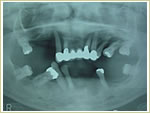

症例2 63歳 女性 画像拡大

治療前 治療後